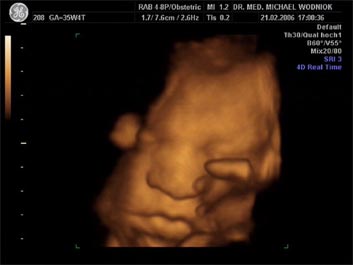

Weitere Ultraschalluntersuchungen sind in der 10./20./30. Schwangerschaftswoche gemäß den Mutterschaftsrichtlinien vorgesehen. Bei erkennbaren Risiken werden  weitere Untersuchungen angeschlossen. Spezielle Ultraschalluntersuchungen zum Ausschluss von kindlichen Entwicklungsstörungen sowie Durchblutungsmessungen der mütterlichen und kindlichen Blutgefäße mittels Farbdopplersonographie gehören zum Leistungsspektrum der Praxis. Auf Wunsch können auch 3D und 4D Untersuchungen angeboten werden.